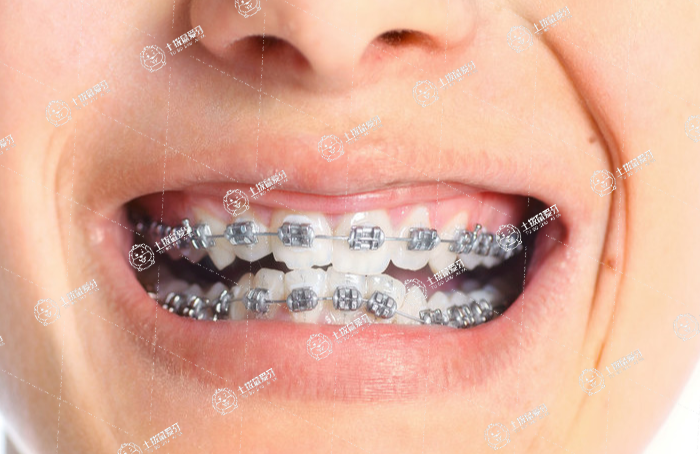

牙齒擁擠矯正

齙牙矯正